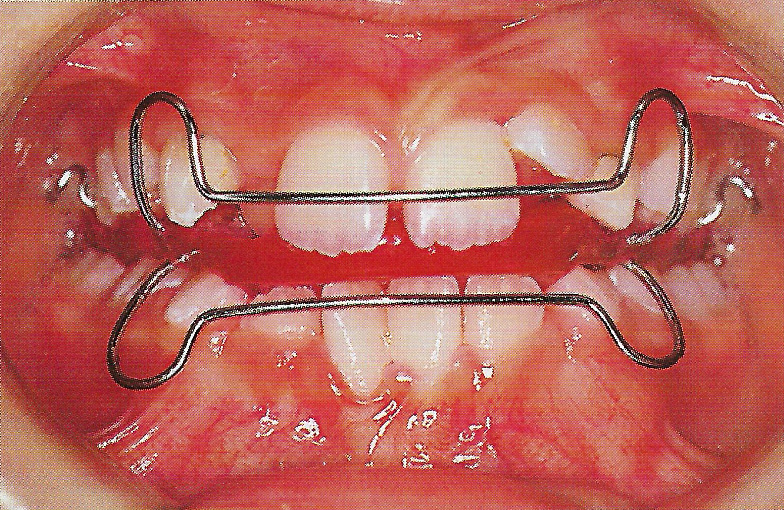

Abb. 1 a bis h Extra- und intraorale Ansicht der Patientin vor Behandlungsbeginn: Kopfbiß beziehungsweise umgekehrter Schneidezahnüberbiß und beidseitiger Kreuzbiß als Folge einer maxillären Hypoplasie sowie hälftenungleicher Mesialbiß infolge mandibulärer Verschiebung nach rechts.

Diese Patientin war zu Behandlungsbeginn 7 Jahre alt. Sie hatte einen hälftenungleichen Mesialbiß infolge mandibulärer Verschiebung mit Kopfbiß beziehungsweise umgekehrter inzisaler Stufe, rechtsseitigem vollem Kreuzbiß und linksseitigem doppeltem Höckerbiß, maxillärer Kompression sowie Platzmangel in beiden Kiefern (Abb. 1 a bis h). Die kephalometrische Analyse ergab eine progene Kieferlagebeziehung, bedingt durch eine unterentwickelte Maxilla bei vertikalem Gesichtsschädelaufbau.